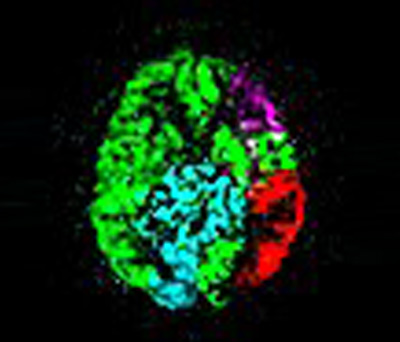

Рис. 1. Небольшая асимметрия гиппокампа (горчичного цвета) у пациента с эпилепсией – левый – 72 см3, правый – 62 см3.

- методики МР волюметрии позволяют с высокой точностью измерить объем гиппокампа (Рис. 1). По данным исследования, без волюметрических измерений асимметрия гиппокампа остается незамеченной врачом-рентгенологом. - методики МР-спектроскопии позволяют оценить концентрацию метаболитов в веществе мозга (NAA, Choline, Creatine), и соотнеся с общим количеством белого и серого вещества в области исследования (вокселе) оценить нарушения метаболизма гиппокампа (Рис. 2).